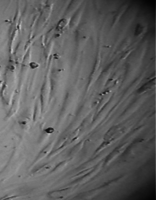

Исследование проведено на первичных культурах дермальных фибробластов и мезенхимальных стромальных клетках человека 4-12 пассажа.

Культуру дермальных фибробластов получали из кожно-мышечной ткани, а культуру мезенхимальных стромальных клеток – из фрагментов крыши черепа абортусов сроком 6-10 недель методом первичных эксплантатов (рис. 1, 2).

Вид монослоя и структура клеток не отличались от обычных в течение всех четырех суток наблюдения (рис. 32).